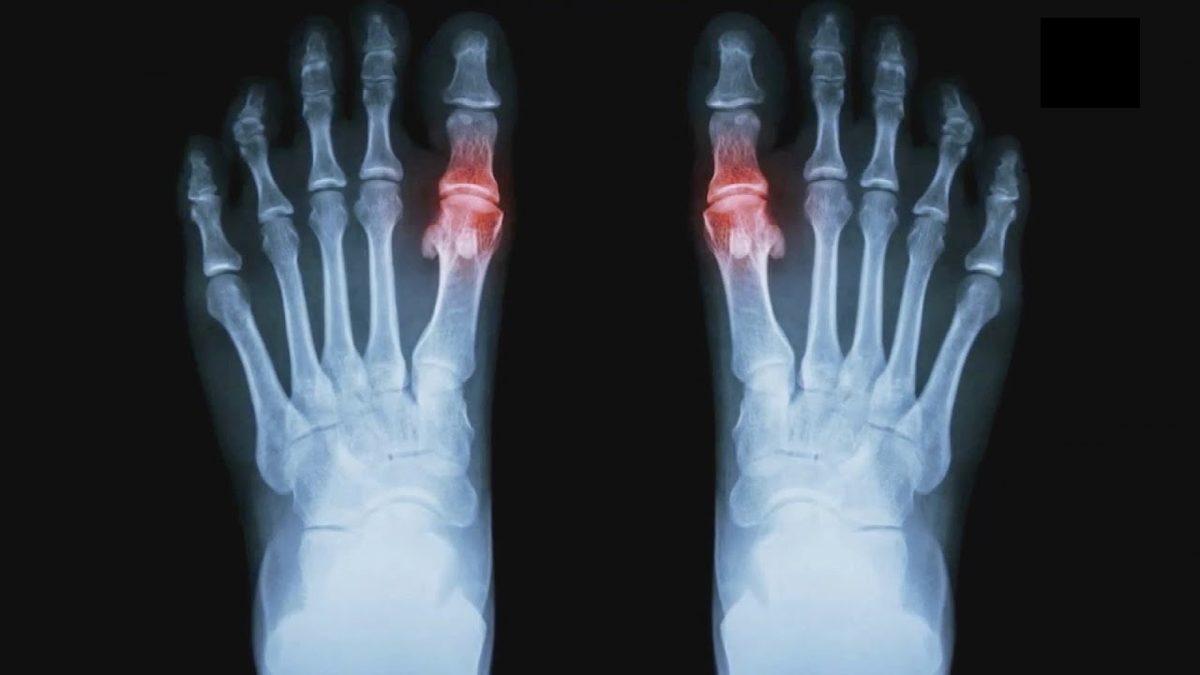

Gut hastalığı tanısı en kolay konulan hastalıklardan bir tanesidir. Atak sırasında röntgen ya da MR çekilmesi ile tespit edilir. Atak anında değilse doktorunuz tarafından istenecek standart bir kan testi sonucuyla da tespit edilebilir. Duruma göre doktor tarafından ürik asit düzenleyici ilaç verilebilir.

Normal kişilerin kanındaki ürik asit seviyesinin üst sınırı 7 mg/dl’dir. Ancak gut hastalarında bu oran 7-9 mg/dl hatta daha yüksek olabilir. Gut hastalığı ürik asidin yüksek olması kaynaklı bir hastalık olsa da tanı konulması için tek etken yüksek ürik asit düzeyi değildir. Kesin bir tanı için atak anında iltihaplı bölgeden sıvı alınıp analiz yapılabilir.